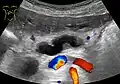

Compression, obstruction or inflammation of the pancreatic duct may lead to acute pancreatitis. The most common cause for obstruction is the presence of gallstones in the common bile duct, a condition called choledocholithiasis. Obstruction can also be due to duodenal inflammation in Crohn's disease.[7] A gallstone may get lodged in the constricted distal end of the ampulla of Vater, where it blocks the flow of both bile and pancreatic juice into the duodenum. Bile backing up into the pancreatic duct may initiate pancreatitis.[8] The pancreatic duct is generally regarded as abnormally enlarged if being over 3 mm in the head and 2 mm in the body or tail on CT scan.[9] Pancreatic duct or parts of pancreatic duct can be demonstrated on ultrasound in 75 to 85% of people.[10]